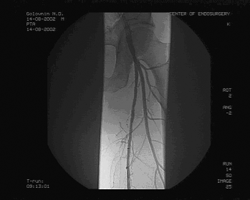

При ангиографии выявлено: субтотальный стеноз правой общей подвздошной артерии (ОПА) в дистальном отделе, бифуркационный стеноз правой общей бедренной (ОБА) артерии 70%, окклюзия правой ПБА в Гунтеровом канале длиной 4 см, окклюзия левой ПБА от устья до подколенной артерии, подколенные артерии и артерии голени проходимы, без гемодинамически значимых сужений. (см. рис. 2)

Рис. 2. Результаты до операционного ангиографического исследования.